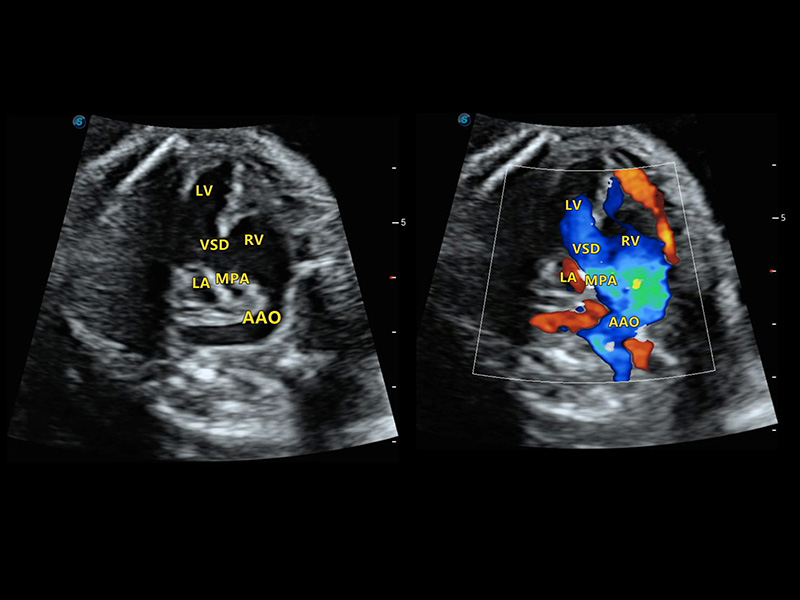

4D HyCoSy mit SPI

Erhöhte Leistungsfähigkeit für mehr Herausforderungen bereit

Die farbkodierte Hysterosalpingo-Kontrastsonografie (HyCoSy) ist eine proprietäre Funktion auf P60 Exp, die die Ankunftszeit von Kontrastmitteln in verschiedenen Teilen der Gebärmutter, der Eileiter und der Eierstöcke klar demonstrieren kann. Dadurch erhalten Kliniker starke und zuversichtliche Beweise, um die Tubenpatenz bei subfertilen Frauen zu untersuchen.

• Eileiter mit 4D HyCoSy

• Eileiter mit 4D HyCoSy mit SPI